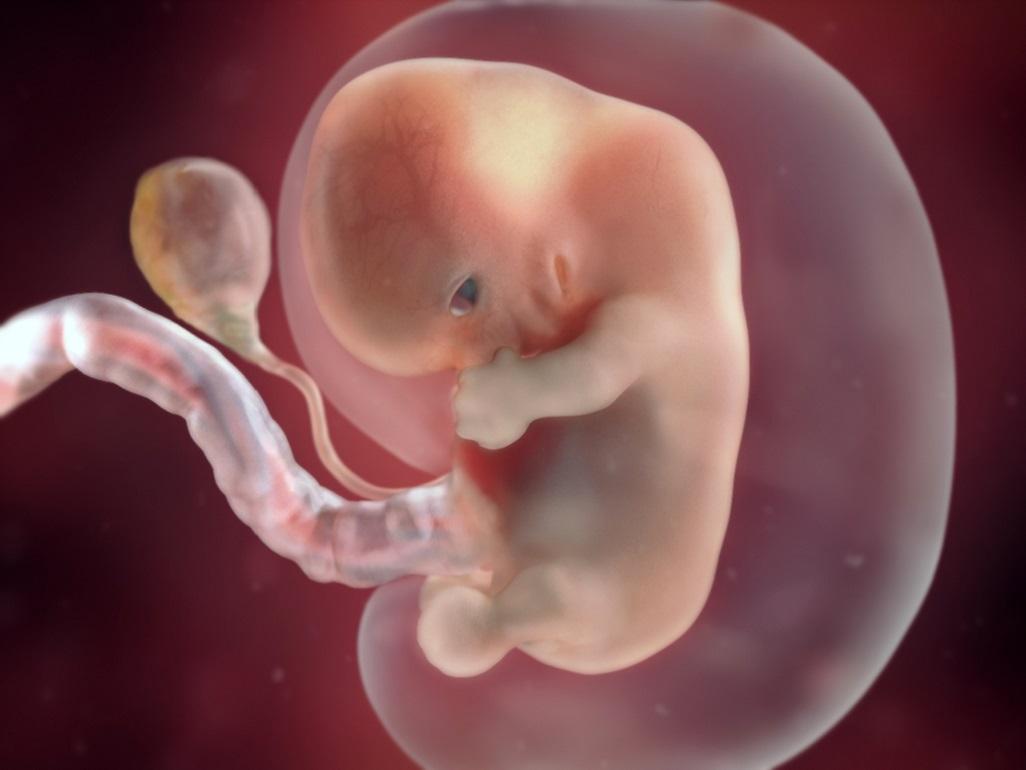

人的受精作用是在输卵管的上段完成。当受精卵在输卵管中段时,胚胎发育就开始了。受精卵一边进行卵裂,一边沿输卵管向子宫方向下行,2~3天可到达子宫。那时的胚胎是由许多细胞构成的中空的小球体,称为胚泡。

受精后约一周,胚泡植入增厚的子宫内股中,这就称为妊娠。胚泡不断通过细胞分裂和细胞的分化而长大,分成了两部分。一部分是胚胎本身将来发育成胎儿;另一部分演变为胚外膜,最重要的是羊膜、胎盘和脐带,胎儿通过胎盘和母体进行物质交换。

在前两个月中,胚胎继续细胞分裂、分化,产生各种细胞,组建各种组织、器官,这是发育中的稚嫩和敏感时期,对各种外界刺激的抵抗力、适应力很差,要十分注意安全,包括孕妇服药、接受辐射或接触其它有害因子等都会影响胎儿的正常发育;到第三个月末,各器官系统基本建成,已称为胎儿。